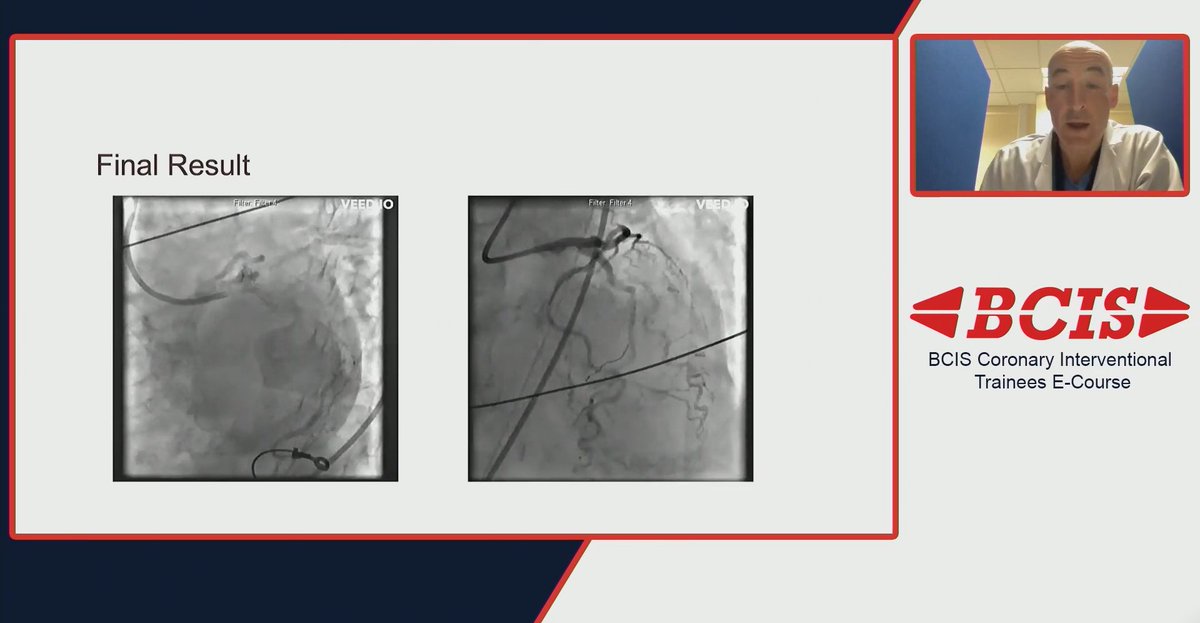

Amazing opportunities for the next generation of interventionists ⬇️

The content from the BCIS Coronary Interventional Trainees e-Course is available to view on-demand! Ft. @ShrillaB @Mariathas83 @ncurzen @kristelly79 @calvert_patrick and more! Take a look here: https://t.co/x4USDr2VUM Members must be logged in to view. #TAVI #CardioEd